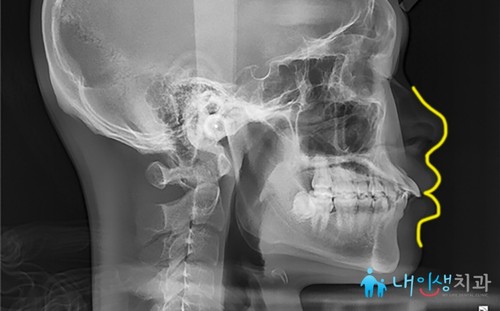

<11개월 후>

교정 치료를 진행하고

11개월이 지난 모습입니다.

잇몸뼈에 자리한 스크류가

발치 과정 없이도 치아가 전체적으로

움직일 수 있도록 도와주고 있어요.

위쪽 치아 전체가 후방 이동하면서

뻐드러져 있던 앞니가

많이 개선된 모습을 보이죠.

이로 인해 입술 돌출 증세도

많이 호전된 상황입니다.